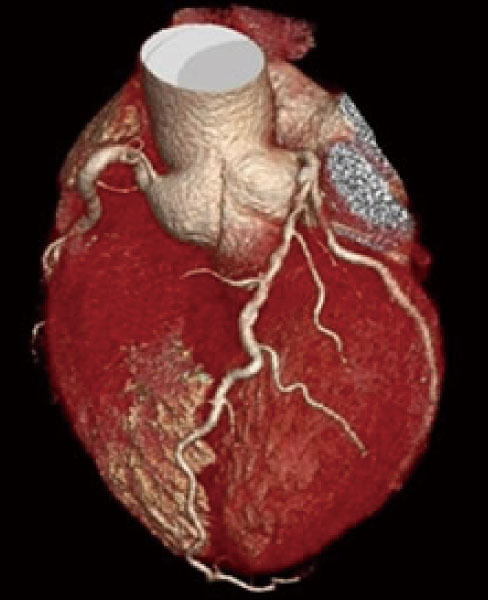

心臓

キヤノンメディカルシステムズ社製 Aquilion ONE